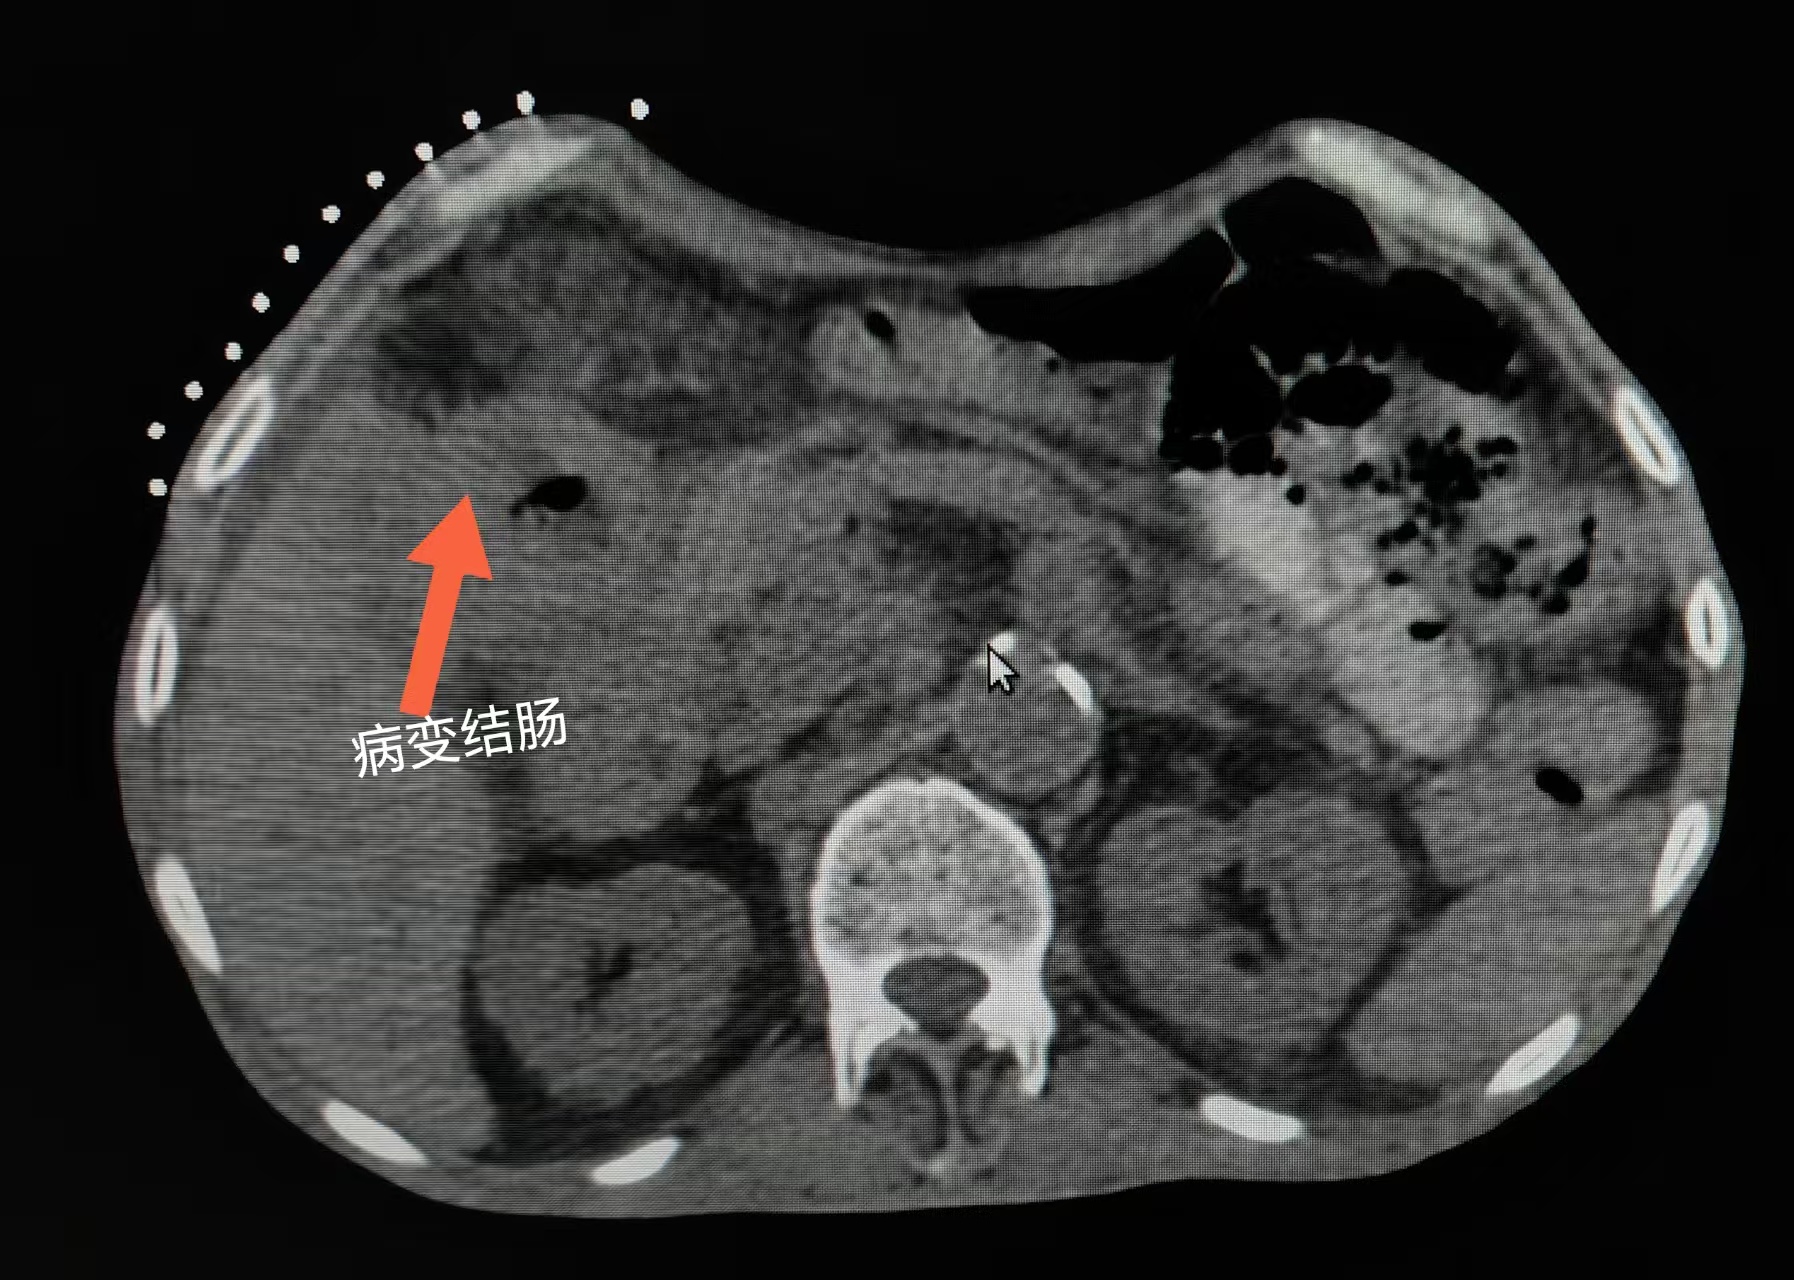

患者高先生自2025年初出现间断上腹痛伴体重下降。4月于石景山医院消化科就诊,腹部CT提示升结肠壁增厚,但肠镜检查未见异常。在消化科医生建议下,患者接受二次肠镜,发现结肠肝曲粘膜肿胀,病理结果仍未见恶性细胞。5月,患者于外院进行第三次肠镜,提示病变与狭窄,但病理仍未明确诊断。

6月初,患者家属求助石景山医院肿瘤科张利锋主任。张主任综合研判患者影像学资料(CT、PET-CT),高度怀疑肠道恶性肿瘤,但亟需病理确诊。考虑到多次肠镜取检未果,张主任决定采用CT引导下结肠占位穿刺活检术。

6月10日,手术在CT实时引导下精准进行。张利锋主任操作细致,成功获取病变组织。术后患者无任何不适,病理结果明确为结肠腺癌。患者随即依据该诊断,开始规范化抗肿瘤治疗。